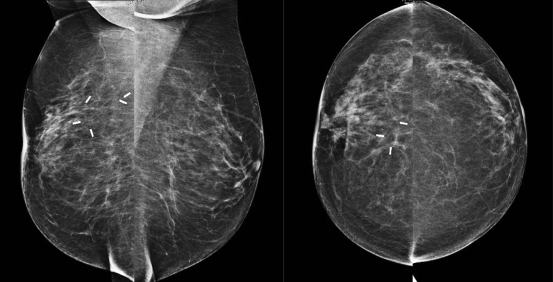

BI-RADS-classificatie 3: waarschijnlijk benigne

Een BI-RADS 3-classificatie wordt gegeven aan afwijkingen met een zeer kleine kans op een maligniteit (tussen 0 en ≤ 2 %) en houdt in dat de afwijking minstens eenmaal wordt gecontroleerd, zes maanden na het eerste onderzoek.

Er zijn meerdere prospectieve studies die de veiligheid en de effectiviteit van deze methode (controle in plaats van biopsie) aantonen in geval van:

• niet-verkalkte, scherp begrensde ronde of ovale massa, die in beeld komt op het mammogram, maar niet palpabel is;

• veldje asymmetrisch klierweefsel, dat er op zichzelf benigne uitziet;

• solitair gelegen groepje puntvormige, dat wil zeggen benigne uitziende calcificaties;

• echografisch beeld van fibroadenoom (fig. 8) of een gecompliceerde cyste, dat wil zeggen met troebele inhoud.

In Nederland wordt bij een BI-RADS 3-afwijking vaak toch gekozen voor punctie, omdat er dan geen controleperiode hoeft te volgen. Dit is echter niet altijd mogelijk of gewenst, er zullen altijd situaties zijn waarbij een controle geprefereerd wordt boven een punctie.

Figuur 8

Echografische afbeelding van een scherp begrensde, ovale, parallelle massa in het mediale bovenkwadrant van de rechtermamma, passend bij een fibroadenoom. Ten tijde van het eerste onderzoek wordt hiervoor een BI-RADS 3 afgegeven. Als de massa na zes maanden onveranderd is gebleven, dan wordt de classificatie een BI-RADS 2 en is verdere controle niet meer nodig.